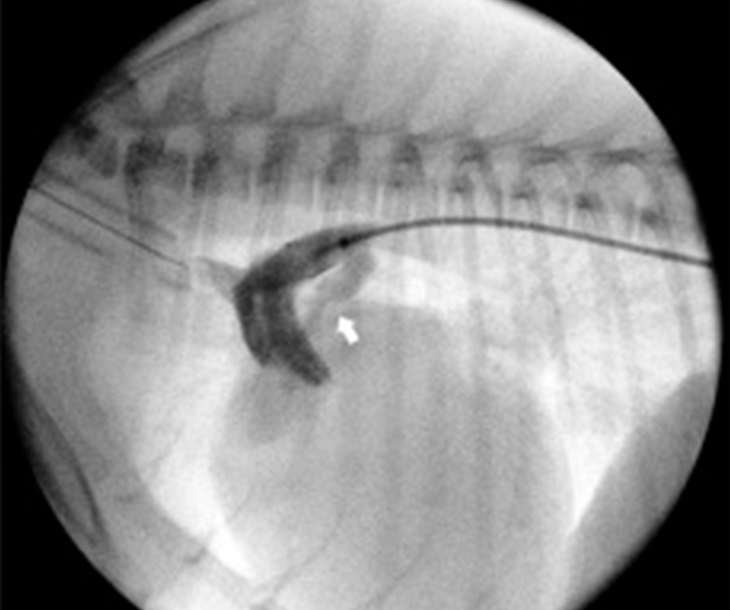

동맥관 개존증(PDA) plug

PDA plug 삽입술은 동맥관 개존증(Patent Ductus Arteriosus, PDA)을 치료하기 위한 중재적 시술로, 개방된 동맥관을 폐쇄하기 위해 특수한 금속 장치(plug)를 혈관내로 삽입하는 최소침습적 치료법입니다. 일반적으로 대퇴동맥 또는 정맥을 통해 카테터를 삽입하여, 심장 초음파와 혈관조영술의 도움으로 정확히 동맥관 위치를 확인한 후 plug를 배치합니다. 시술은 마취하에 진행되며, 수술적 절개없이 안전하고 효과적으로 PDA를 폐쇄할 수 있어 회복이 빠르고 합병증 발생률이 낮습니다.